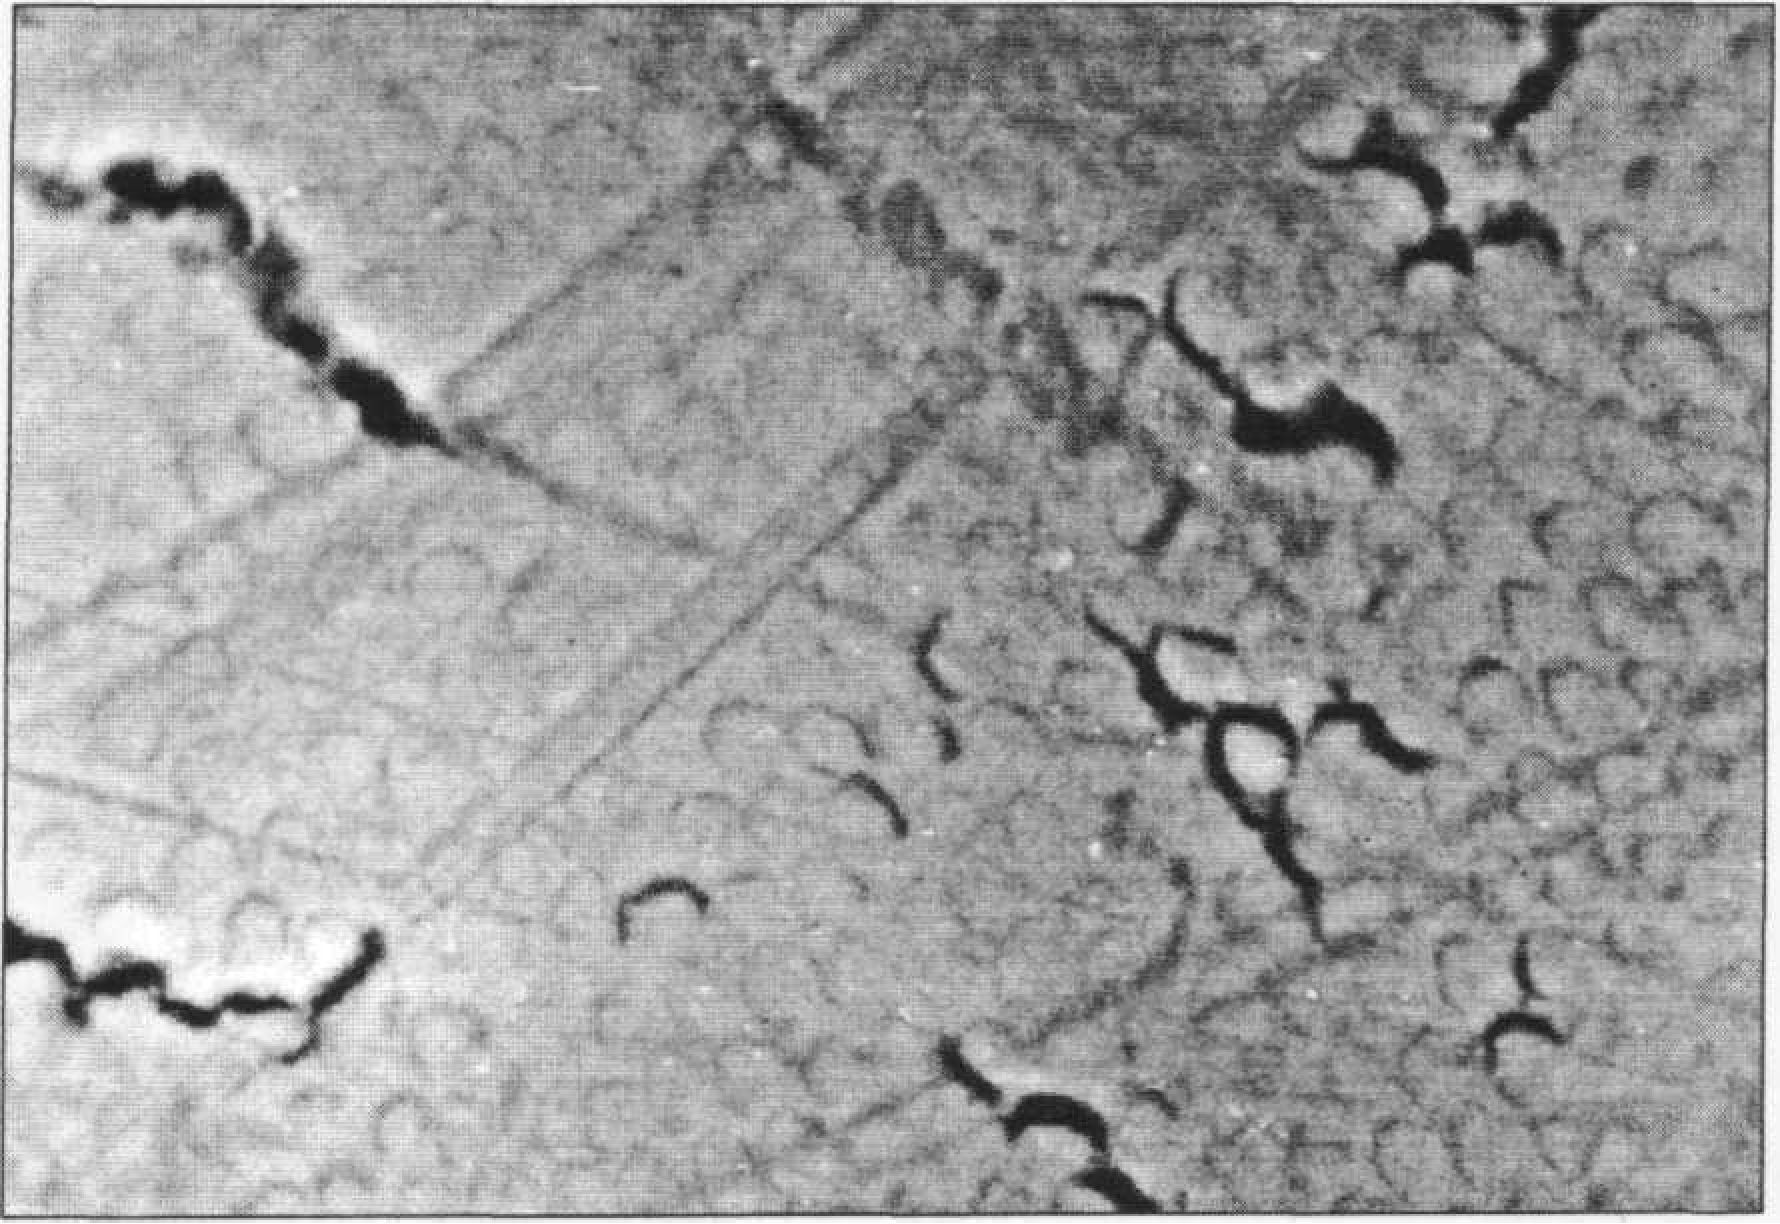

Полосы и царапины идут на зубе в различных направлениях. Мелки трещины огибают головки призм, крупные чаще располагаются на вестибулярной поверхности параллельно вертикальной оси зуба. Как правило, они заполнены гравиеподрбными отложениями, аморфным веществом. В поверхностном слое эмали образуются трещины, микродефекты, п`ризмы слабо конту- рируют (рис. 106).

Это касается эмали, располагающейся под зубным камнем. В пришеечной области об и наруживается усиление линии Ретциуса и шлиф зуба. Более четкий рисунок призм на этом участке свидетельствует о пониженной минерализации, а, следовательно, о появлении или сохранении зон, отличающихся пористостью. Кроме описанных возрастных особенностей, специфические преобразования происходят в области фиссур премоляров и моляров. Нередко наблюдается их спонтанное запечатывание естественным путем. В таких случаях в фиссурах обнаруживаются плотные высокоминерализованные образования. В группе старшего возрастного периода (45-70 лет) отмечается дальнейшее повышение однородности эмали зубов с сохранением призменной структуры во всех слоях, кроме поверхностного, где на большей части она беспризменная. Полосы Гунтера-Шрегера контрастны, линии Ретциуса, напротив, выделяются слабо. Уменьшение объема органического компонента эмали, размеров микропространств приводит к снижению количества воды в твердых тканях зуба. Отмечается уплотнение кристаллической решетки — за счет замещения ионов ОН на F. Поверхностный слой эмали зрелых и «старых зубов», как правило, становится беспризменным на десятки мкм. Зубы отличаются значительной стертостью бугров и режущего края. Площадь стертости с возрастом увеличивается. В сканирующем электронном микроскопе видны отдельные призменные участки поверхности эмали, маскирующиеся пелликулой, причем головки призм выступают над ее уровнем. На поверхности интактной эмали выявляется значительное число царапин, борозд, трещин (рис. 105).